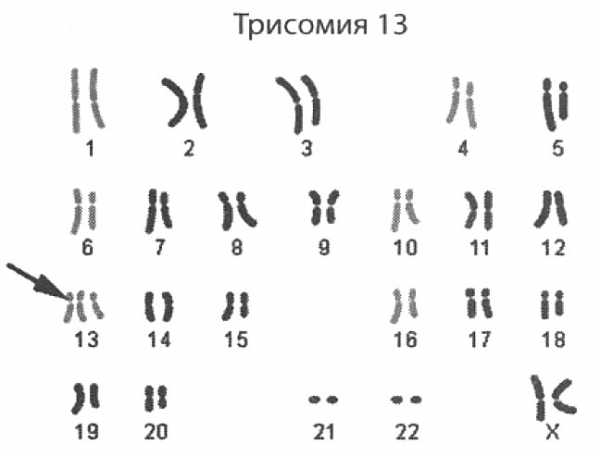

Синдром Патау – генетическое заболевание человека. Эта аномалия происходит, когда в хромосомном наборе зародыша утраивается 13-я хромосома. Синдром Патау приводит к многочисленным заболеваниям нервной системы, глаз, мышечной ткани и требует длительного и обстоятельного лечения.

По статистике один ребенок с этим генетическим заболевание рождается на десять тысяч здоровых детей. Страшному заболеванию подвержены как мальчики, так и девочки. Основная причина развития аномалии – трисомия 13-ой хромосоме. То есть, при нормальном кариотипе ребенок с этим синдромом имеет еще одну 13-ую хромосому.

Синдром Патау или синдром трисомии 13 хромосомы – тяжелая генетическая аномалия, связанная с присутствием в хромосомном наборе лишней копии (трисомии) 13 хромосомы.

Главной причиной развития синдрома Патау является дополнительная третья копия 13-й хромосомы в генетическом коде ребенка.

Количество хромосомных заболеваний огромно и одним из них является синдром Патау. Кариотип пациента с подобным диагнозом изменен, что отображается на работе всего организма. Патология сказывается на строении скелета, работе нервной, выделительной, репродуктивной и сердечно-сосудистой систем.

Синдром Патау: кариотип и общая информация

Для начала стоит разобраться с общими данными. Что собой представляет и как развивается синдром Патау? Хромосомы при подобной патологии не расходятся в процессе образования гамет или зиготы, что приводит к массе нарушений в процессе эмбрионального развития.

Синдромом Патау называют врожденное заболевание, которое связано с трисомией 13-й пары хромосом — ребенок получает лишнюю хромосому. Формула кариотипа в данном случае может выглядеть следующим образом: 47, XX, 13 + (для девочек), 47, XY, 13 + (для мальчиков). Это крайне опасное и тяжелое заболевание, которое сопровождается формированием множественных пороков развития — часто они не совместимы с жизнью, поэтому ребенок гибнет еще в утробе матери.

Синдром Патау – хромосомное заболевание, обусловленное наличием дополнительной копии 13-ой хромосомы (трисомия по 13-ой хромосоме).

По сути своей синдром Патау представляет собой патологическое состояние генома человека, при котором обнаруживается лишняя тринадцатая хромосома. В связи с этим заболевание получило научное название трисомия 13. Частота этой патологии достигает 1:7000, но обычно этот показатель колеблется в районе 1:10000-1:14000. Половое соотношение пациентов с трисомией по 13 хромосоме приблизительно 1:1.

Генетика

В основном, встречаются две генетические формы трисомии по тринадцатой хромосоме:

- Простая трисомия – три хромосомы одного вида свободно существуют и реализуют генетический потенциал.

- Робертсоновскаятранслокация – две хромосомы остаются свободными, а третья сливается длинными плечами с другой акроцентрической хромосомой (например, с 14 или 21). Так как акроцентрические хромосомы в коротких плечах имеют лишь гены рРНК, многократно продублированные в кариотипе, их функциональность в большинстве случаев сохраняется.

В любом случае кариотип больного синдромом Патау определяется формулой 47 XX (XY) 13+. Иногда регистрируются случаи неробертсоновскихтранслокаций, изохромосомной и мозаичной формы трисомии 13.

Патологическая картина и симптоматика у генетических разновидностей синдрома Патау не отличается. У 3/4 пациентов обнаруживается лишняя 13 хромосома, оставшаяся четверть больных страдают от вовлечения 13 пары хромосом в транслокацию, что в 75% случаев происходит из-за мутации denovo (новой, возникшей самостоятельно) – так называемой, «генетической ошибки». Исследования наследственности синдрома Патау показывают, что остальные 25% случаев трисомии 13 происходят из-за передачи транслокализованой тринадцатой хромосомы от одного из родителей. При этом риск повторения случая у следующего ребенка (возвратный риск) составляет 14%.